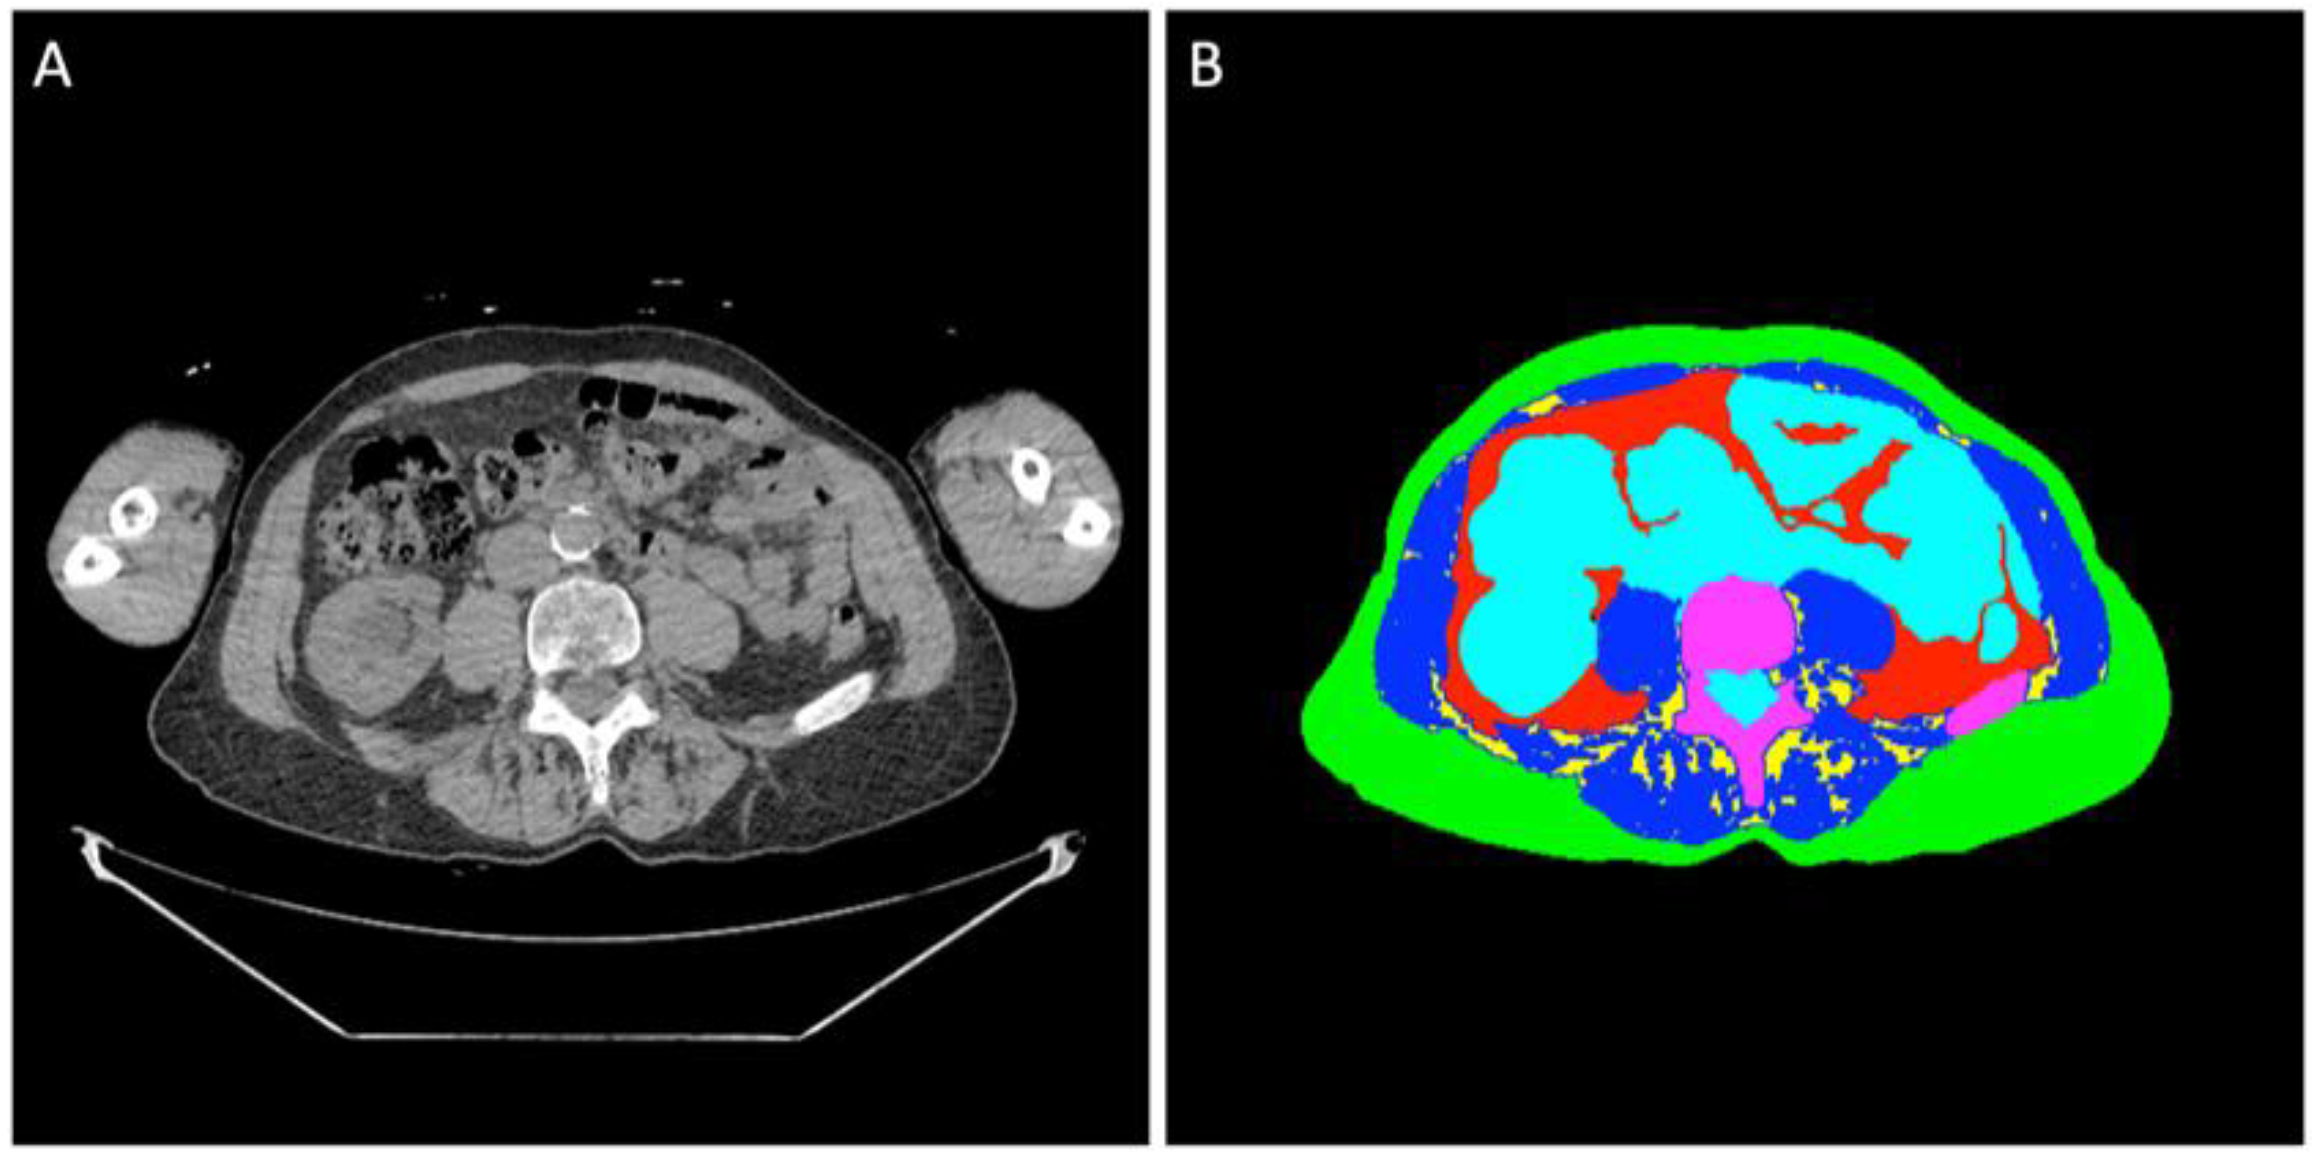

2.2. Image Analysis